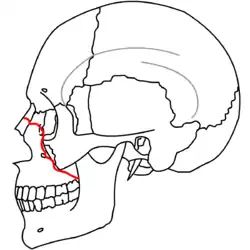

At the beginning of the 20th century, René Le Fort mapped typical locations for facial fractures; these are now known as Le Fort I, II, and III fractures (right).[7] Le Fort I fractures, also called Guérin or horizontal maxillary fractures,[14] involve the maxilla, separating it from the palate.[15] Le Fort II fractures, also called pyramidal fractures of the maxilla,[16] cross the nasal bones and the orbital rim.[15] Le Fort III fractures, also called craniofacial disjunction and transverse facial fractures,[17] cross the front of the maxilla and involve the lacrimal bone, the lamina papyracea, and the orbital floor, and often involve the ethmoid bone,[15] are the most serious.[18] Le Fort fractures, which account for 10–20% of facial fractures, are often associated with other serious injuries.[15] Le Fort made his classifications based on work with cadaver skulls, and the classification system has been criticized as imprecise and simplistic since most midface fractures involve a combination of Le Fort fractures.[15] Although most facial fractures do not follow the patterns described by Le Fort precisely, the system is still used to categorize injuries.[5]

| Le Fort II fractures | |